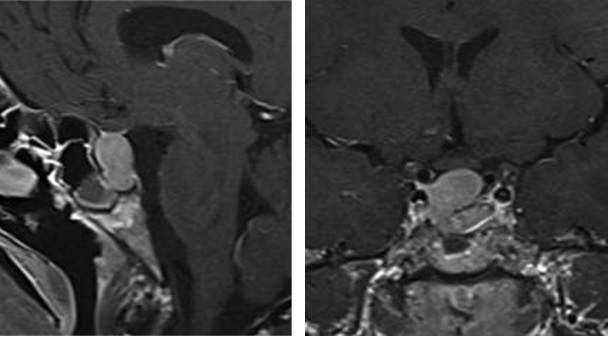

西门子MAGNETOMAera 1.5T纪元四度磁共振可进行神经系统、脊柱、四肢关节、腹部、心脏、血管等全身各个系统的不同疾病的检查,而且能进行波谱分析,对肿瘤的性质鉴定有很高临床价值。对CT无法发现的超早期脑梗塞病变具有无可替代的作用,能发现发病后几分钟内的病灶,为挽救患者生命和改善预后、减少致残率赢得时间,必将进一步提升诊疗水平,为临床诊断提供更有力的硬件支持,为广大患者带来福音。